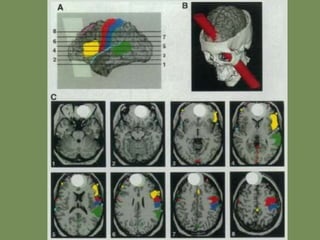

La base neurológica de la menteTodos los procesos, funciones o estados mentales conscientes/inconscientes están cableados por circuitos neurales y localizados de algún modo en zonas cerebrales.

Lesiones fisiológicas, o alteraciones químicas o farmacológicas modifican esos procesos o los interfieren.

Ahora se piensa en una unidad causal cerebro-mente separada del resto del cuerpo. Este paradigma podría denominarse neurocentrismo, y fue anticipado por Spinoza.

La lesión de PhineasGage estudiada por Damasio

La lesión dePhineasGage estudiada por Damasio